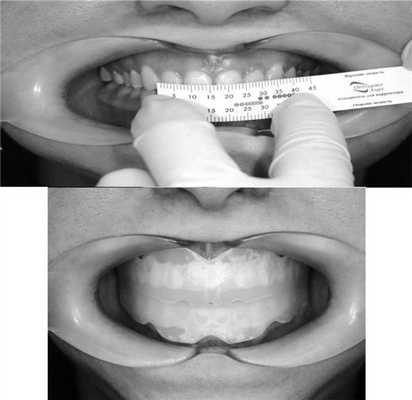

Комплекс миогимнастики с аппаратом ОЭ Корректор

При применении Корректора определяется только размер, так как эластопозиционер моделирует оптимальную окклюзию без увеличения разобщения зубных рядов по оклюзионной плоскости в разных участках. Эластичная каппа для коррекции прикуса Корректор выпускается 8 типоразмеров. Каждый типоразмер соответствует длине 4 резцов, измеренной по экватору вестибулярной поверхности ВЧ и НЧ (рис. 1). Рис. 1. Подбор Корректора (а); в полости рта (б).